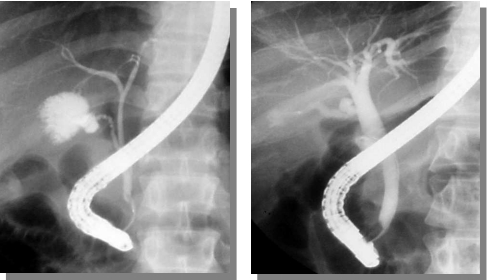

开展逆行性胰胆管造影、经十二指肠镜乳头括约肌切开成形术、经十二指肠 镜胆总管结石取出术、经十二指肠镜鼻胆管引流术、经十二指肠镜胆管狭窄扩张术、经十二 指肠镜胆管支架置入术、经十二指肠镜胆总管碎石术。

ERCP—治疗胆总管结石的法宝

患者,男性,82岁,因发热来我院呼吸内科就诊,抗感染治疗多日不见好转,后因腹痛、巩膜黄染、肝功能异常做了腹部彩超、CT等检查,发现罪魁祸首─胆总管结石,最后转入消化内科做了内镜下取石。所以,早期及时治疗对于胆总管结石的康复尤为重要。胆总管结石对有些人来说比较陌生,下面用一张图帮助大家认识它。图中数字3所示为胆总管结石胆总管结石的病因1.原发性胆总管结石:多为棕色胆色素结石或混合性结石,形成的诱因有:胆道...